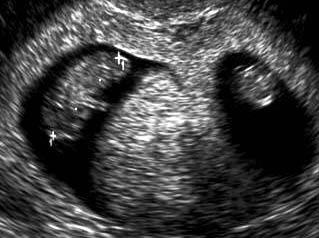

香港结构超声波照片

结构性超声波, 四维 香港, 四维结构性超声波 结构性超声波, 四维 结构性超声波, 四维 香港, 四维结构性超声波 结构性超声波, 四维 香港, 四维结构性超声波 结构性超声波, 四维 结构性超声波, 四维 结构性超声波, 四维 香港, 四维结构性超声波 结构性超声波, 四维 香港, 四维结构性超声波 结构性超声波, 四维 结构性超声波, 四维